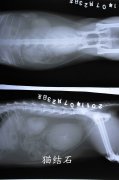

宠物X光机拍动物全身图片

近有客户想要了解 下宠物X光机拍片的突显,以下使用我公司生产的宠物X光机拍摄的照片。如果您需要采购宠物X光机。可以致电:0536-8322186或15628738102!...更多 -